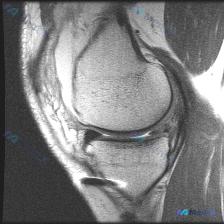

看到一个有意思的影像读片问题,整理了完整的分析思路分享给大家。 病例/影像基本信息 这是一张单幅膝关节矢状位T1加权MRI影像,问题是观察图像中是否存在软骨异常。 影像本身特点:图像有明显噪声(颗粒感重),对比度一般,解剖结构轮廓可辨认,但精细细节分辨率受限,属于质量不佳的单幅影像。 系统性影像观察...